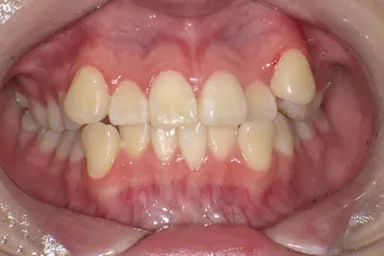

13歳8か月の女子(初診時:写真a)

主訴は左上に八重歯がある。右側Angle ClassII 左側Angle Class I、FMA 36.6°、A.L.D.(凸凹の量/上顎 -10.0mm、下顎 -4.0mm)

a:初診時